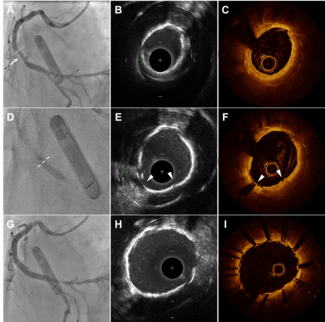

In vitro experiments. An originally developed coronary circulation model was employed to simulate multiple sequential coronary stenoses within the same coronary artery (Figure 2). The in vitro model consists of a pump, a systemic and coronary circulation, and constrictors. The pump produces a pulsatile flow at 60 rpm. Distilled water was used as the perfusate. The systemic and coronary circulation is made of silicone rubber tubes that mimic the human arterial system. The inner diameter of the coronary artery is 4 mm and the inner diameter of the aorta is 12 mm. The pressure and flow in the coronary artery are adjustable by a valve placed in the aorta. The coronary artery bifurcates to a main and a side branch. The main and side branches merge together peripherally. Three constrictors are placed in the main coronary artery to create multiple sequential stenoses at intervals of 40 mm. Another constrictor placed in the side branch was used to adjust Pw of the main coronary artery with a range of 0 to 20 mm Hg. FFR

The in vitro model consists of a pump, a systemic and coronary circulation, and constrictors. The pump produces a pulsatile flow at 60 rpm. Distilled water was used as the perfusate. The systemic and coronary circulation is made of silicone rubber tubes that mimic the human arterial system. The inner diameter of the coronary artery is 4 mm and the inner diameter of the aorta is 12 mm. The pressure and flow in the coronary artery are adjustable by a valve placed in the aorta. The coronary artery bifurcates to a main and a side branch. The main and side branches merge together peripherally. Three constrictors are placed in the main coronary artery to create multiple sequential stenoses at intervals of 40 mm. Another constrictor placed in the side branch was used to adjust Pw of the main coronary artery with a range of 0 to 20 mm Hg. FFR measurements were conducted using a 0.014-inch pressure wire (St Jude Medical). After creating 3 sequential stenoses with variable degrees, a pressure wire was advanced to a position distal to the most distal stenosis. Pw was obtained during a temporary occlusion of the distal part of the main coronary artery. After releasing the temporary occlusion, the pressure wire was slowly pulled back from the distal coronary artery to the ostium of the coronary artery, thereby recording Pd, Pdist, Pprox, and Pa. The pressure wire was completely pulled back into the guiding catheter to verify that no drift had occurred each time. The pressure wire was advanced again to the position distal to the most distal artery. FFR(X)true was obtained when all the stenoses except for stenosis X were released. FFR(X–)true was obtained when stenosis X was completely released. The

Validation of Equation A. A total of 30 different 3 sequential stenoses were created. First, the baseline pressure data including Pa, Pd, Pw, Pdist, and Pprox were obtained. FFR(X)app and FFR(X)pred were calculated using the above mentioned equations. Then, the proximal and distal stenoses were removed. The pressure data including P´a and P´d were obtained and FFR(X)true was calculated. A representative case is presented in Figure 3.

the baseline pressure data including Pa, Pd, Pw, Pdist, and Pprox were obtained. FFR(X)app and FFR(X)pred were calculated using the above mentioned equations. Then, the proximal and distal stenoses were removed. The pressure data including P´a and P´d were obtained and FFR(X)true was calculated. A representative case is presented in Figure 3.

Validation of Equation B. A total of 30 different 3 sequential stenoses were created. The experiment was conducted using a similar method. Briefly, after obtaining the baseline pressure data, FFR(X–)app and FFR(X–)pred were calculated. Then, the middle stenosis was removed and FFR(X–)true was obtained. A representative case in the validation of equation B is presented in Figure 5.